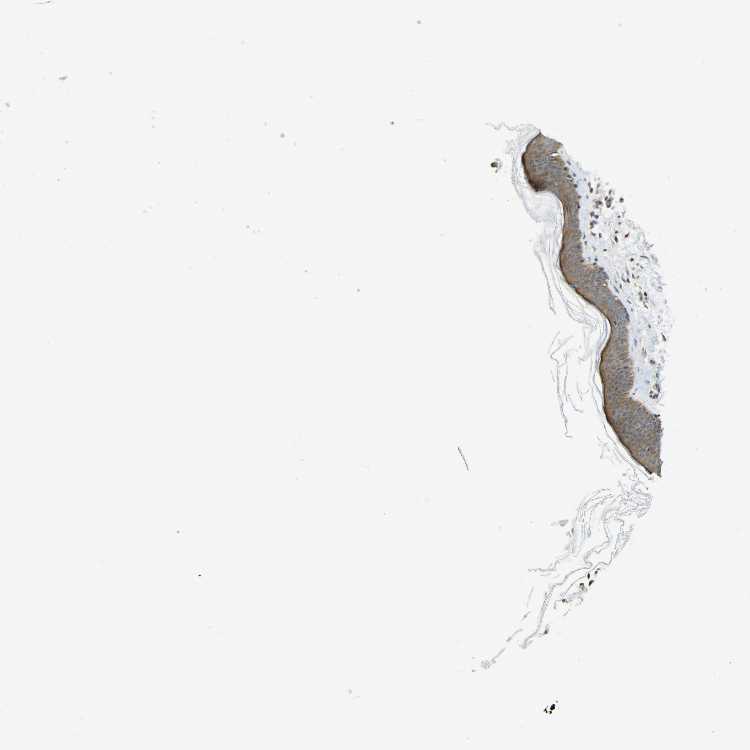

SKIN 1 - Antibody stainingi

Antibody staining in the annotated cell types in the current human tissue is reported as not detected, low, medium, or high, based on conventional immunohistochemistry profiling in selected tissues. This score is based on the combination of the staining intensity and fraction of stained cells.

Each image is clickable and will lead to virtual microscopy that enables deeper exploration of all samples and also displays staining intensity scores, fraction scores and subcellular localization as well as patient and tissue information for each sample.

Antibody HPA063018Antibody CAB013715

Langerhans LowMedium

Fibroblasts MediumMedium

Keratinocytes MediumMedium

Melanocytes LowMedium